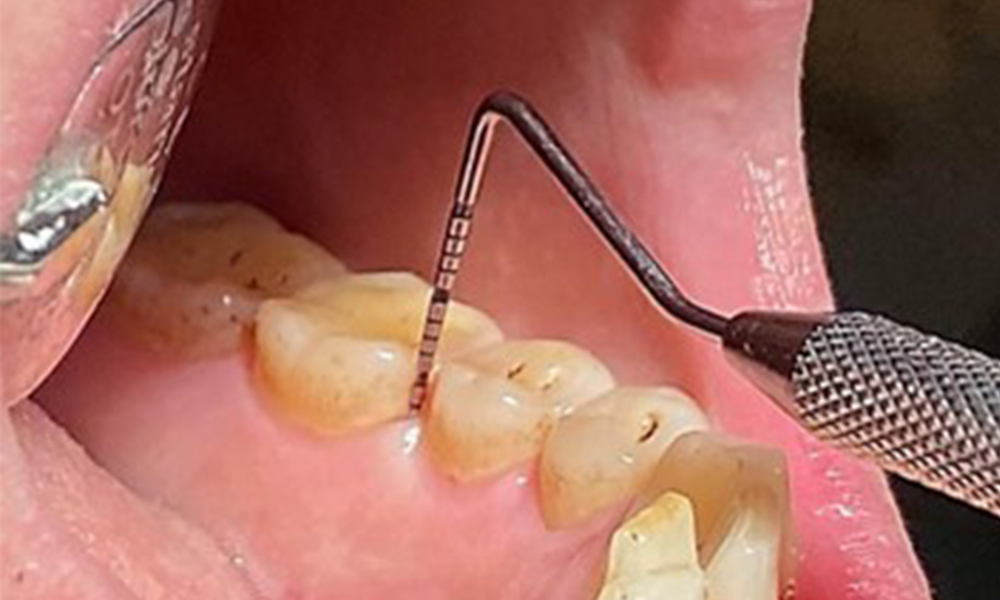

Поради иначе благоприятното общо медицинско състояние, нуждите, определени по време на оралния преглед, ще бъдат решаващи за лечението. От съществено значение ще бъде периодичното определяне на дълбочината на сондиране. Гингивалното кървене намалява при пушачите, поради което клиничната диагноза на пародонтита може да се постави само чрез сондиране (фиг. 7). Поставянето на изключителен акцент върху определянето на индексите на кървене може да замъгли съществуващ пародонтит или гингивит. (5)